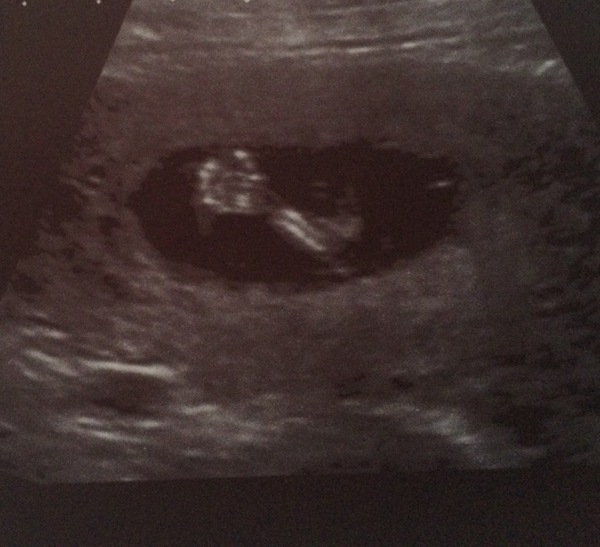

Over the moon to say that our 12 week scan went well. I literally can't stop crying...happy tears. After my mc a couple of years ago I truly had given up hope that I would ever be a mummy to my own precious baby. I can't describe how blessed I feel, that after 9 long years it's finally our turn :,) I know my precious angel in the sky is keeping a close watch over his baby brother or sister xx oh and we are measuring ahead so due date changed to 1st Feb....how's that even possible when it's an ivf baby?? There can't be any mix up with dates lol x

Scan all fine and I spent most of it eyes shut trying not to cry so poor sonographer could get the measurements he needed. I had no idea they move around so much even though so tiny! Thought it would be really grainy and hard to see but it was crystal clear, absolutely incredible. Baby was annoyed at having pressure put on, turned a somersault and then turned his/her back on us! Still in shock. Will have to tell the rest of my family soon!

Carly congratulations!!! What a lovely picture! We are the same - measuring a week ahead despite it being an ivf baby! No idea how that happens!! I'm now actually end of Jan but sneakily staying on here because I like this group!! Xx

But we did get a hand wave at the ultrasound today.